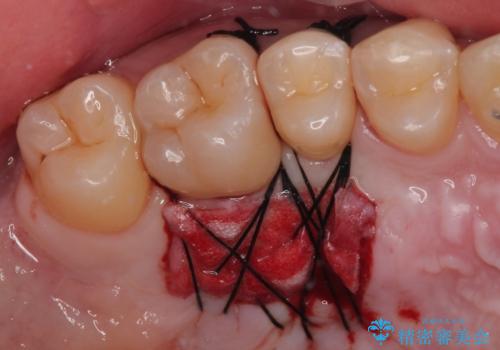

歯肉退縮に対して、上顎からの結合組織移植術(CTG)により、歯根の被覆を行うとともに、歯肉の厚みを増すことで将来の退縮リスクを抑制することとしました。

被覆量が不十分の場合には、追加で手術を行うことで患者様の了解を得ました。

一度の処置で十分に根面被覆ができました。